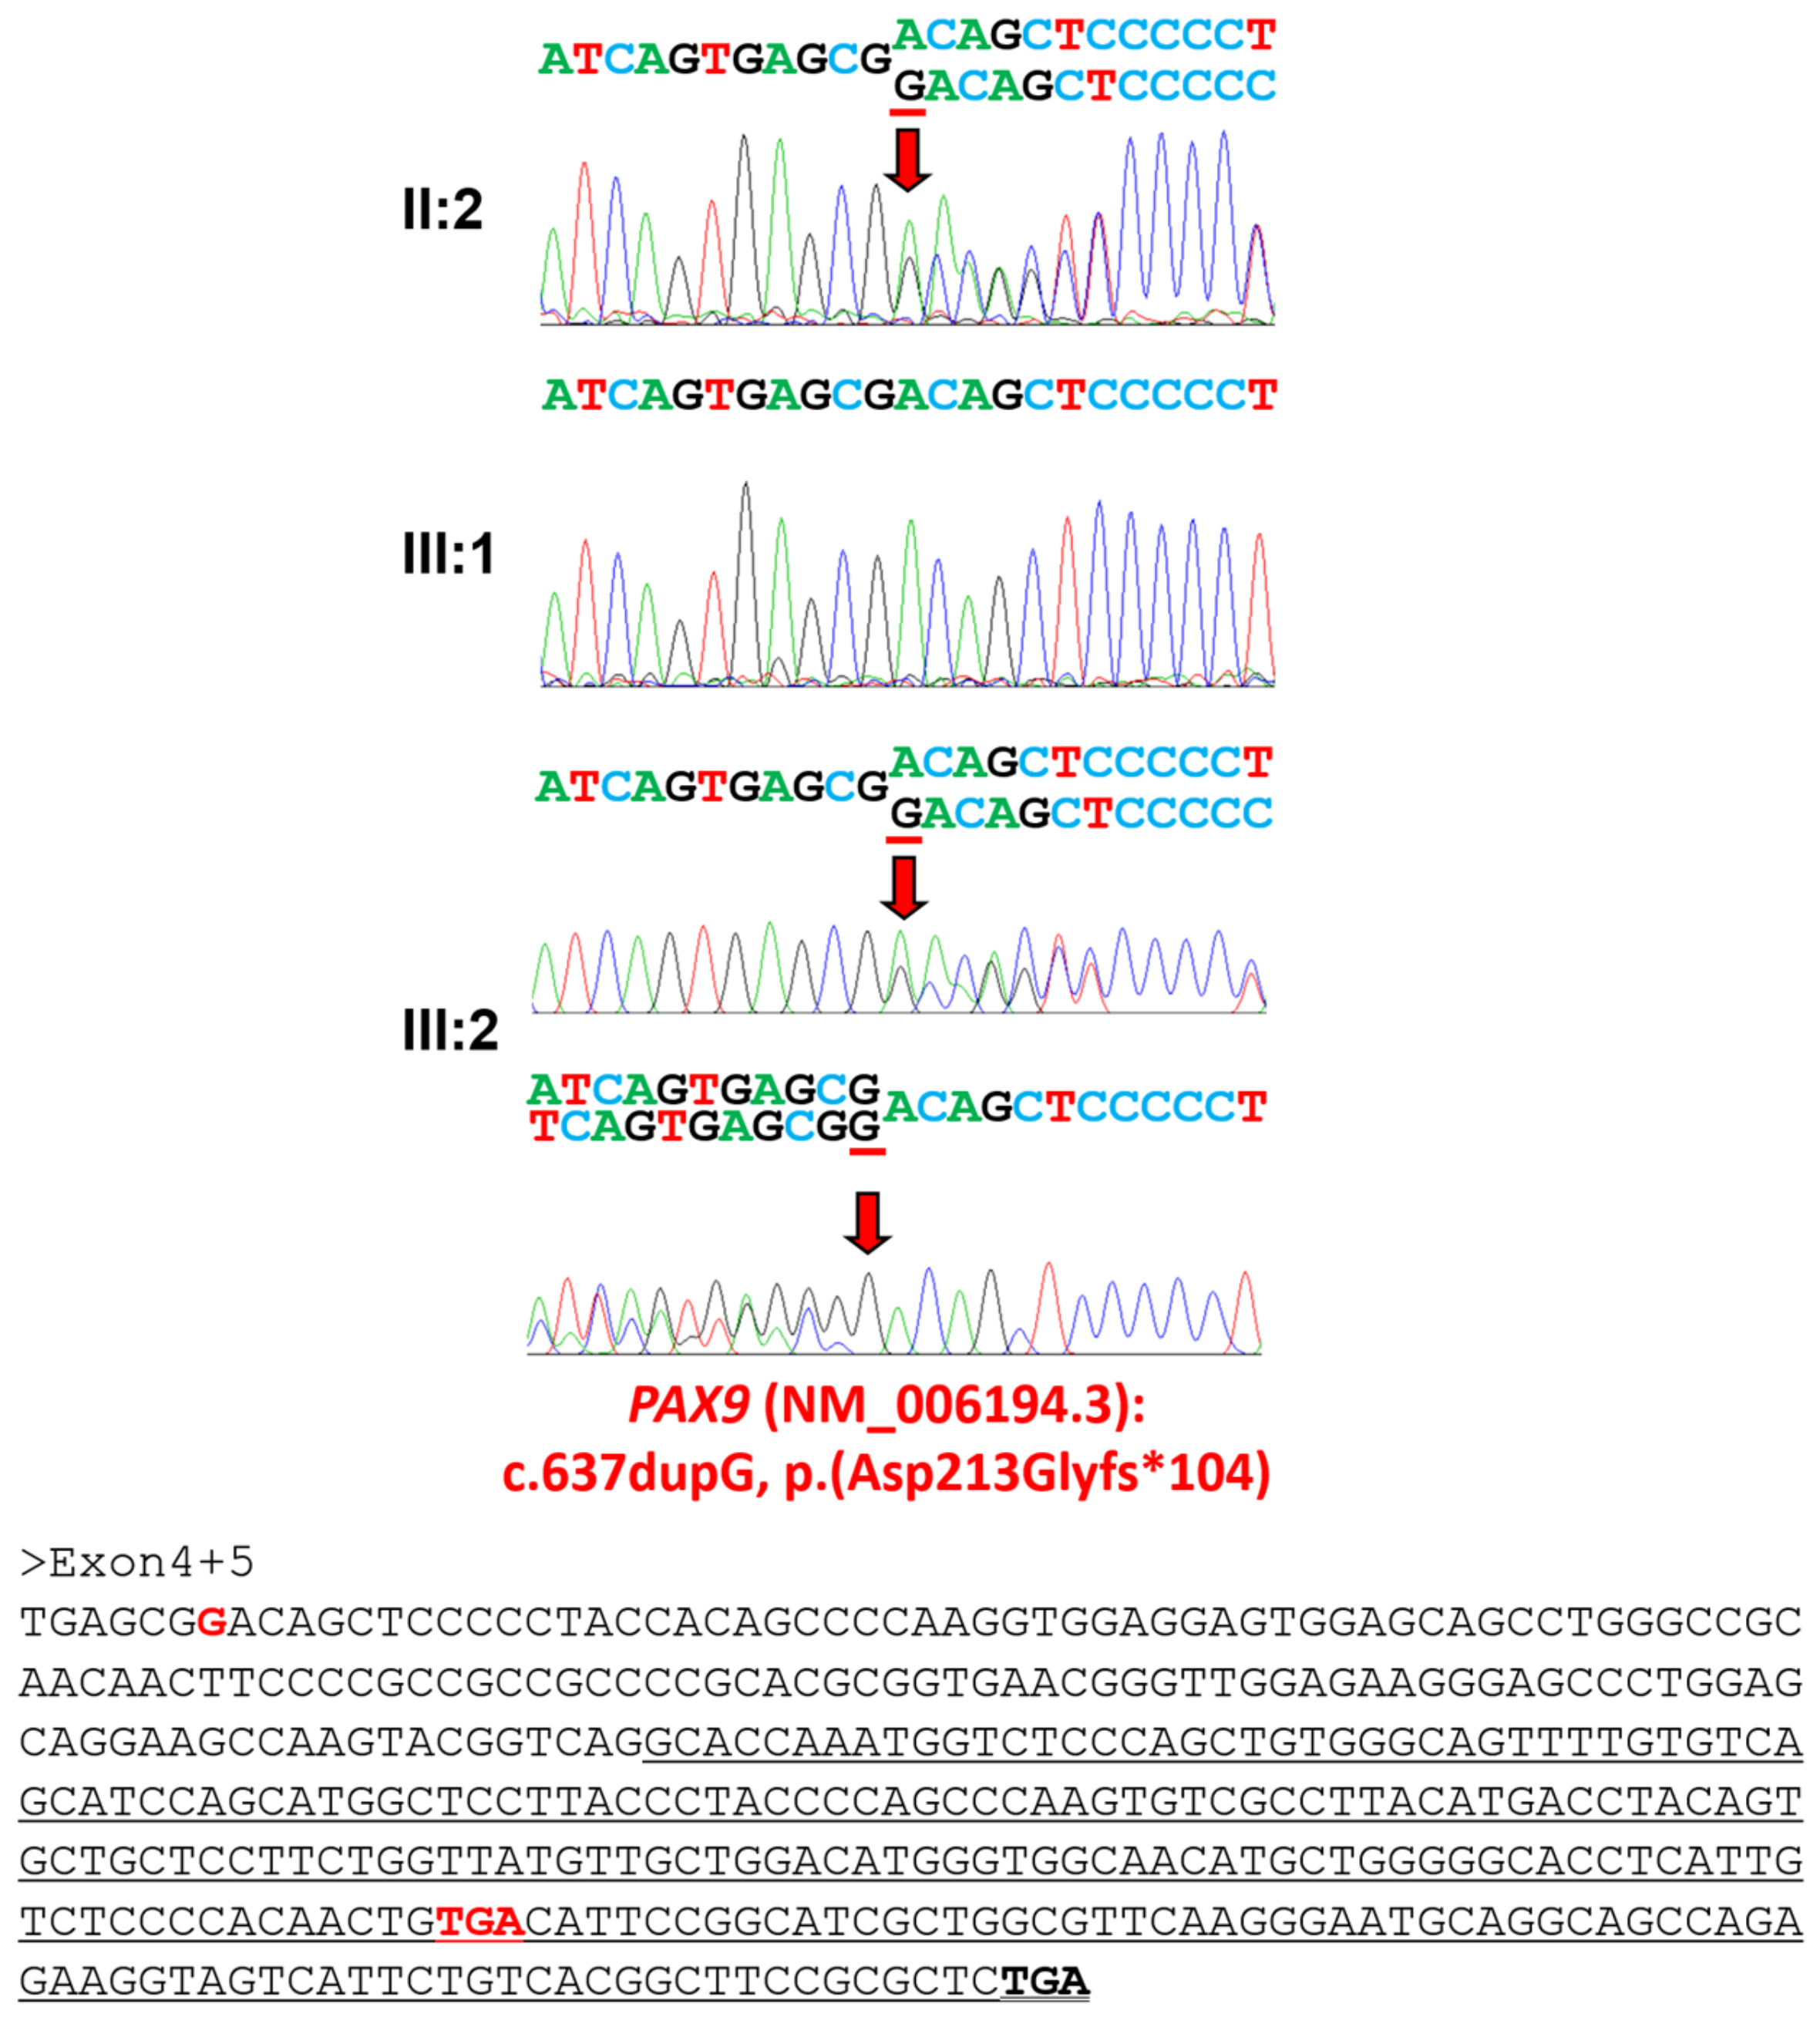

3.2. Family 2